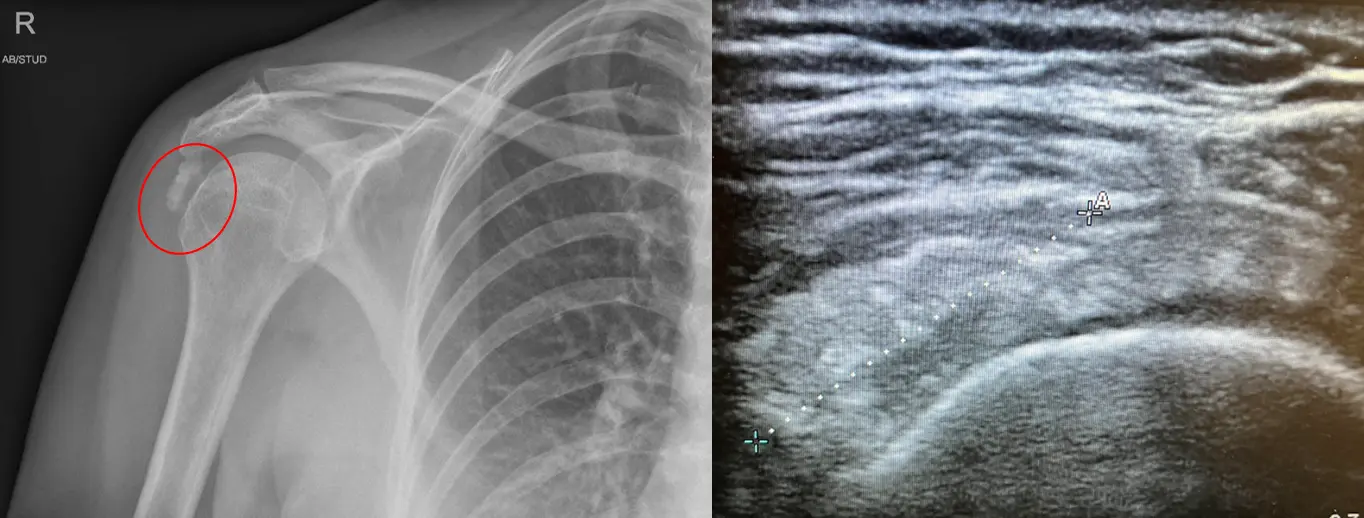

Ο ασθενής με ασβεστοποιό τενοντίτιδα του ώμου χρειάζεται εκτίμηση από εξειδικευμένο Ορθοπαιδικό Χειρουργό. Ο κ. Βλάχος αφού λάβει το ιστορικό σας και σας εξετάσει πολύ προσεκτικά, θα πραγματοποιήσει υπερηχογράφημα με σκοπό να ελέγξει την ακεραιότητα των τενόντων του στροφικού πετάλου, την παρουσία υγρού καθώς και το μέγεθος και την θέση του ασβεστώματος. Επίσης θα χρειαστεί η λήψη μιας ακτινογραφίας ώστε να αποκλειστεί το ενδεχόμενο οστεοαρθρίτιδας ή άλλων παθήσεων του ώμου. Σε συγκεκριμένες περιπτώσεις ο ιατρός θα χρειαστεί να σας παραπέμψει για μαγνητική τομογραφία του ώμου.